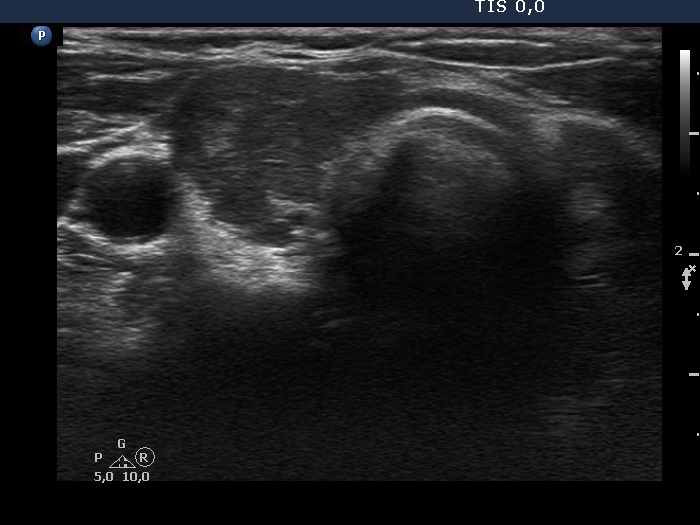

The echogenicity of the nodule - case 2044 (ultrasonographic picture 2)

Right lobe, longitudinal scan

Right lobe, another transverse scan. This part of the lobe is deeply hypoechoic.